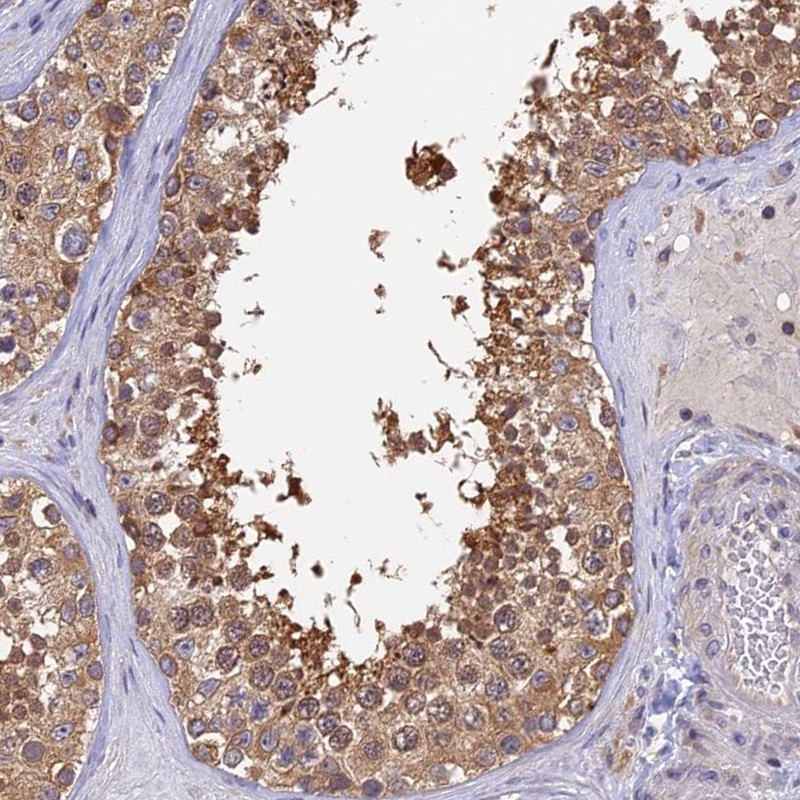

Immunohistochemical staining of human testis shows moderate cytoplasmic positivity in cells in seminiferous ducts.